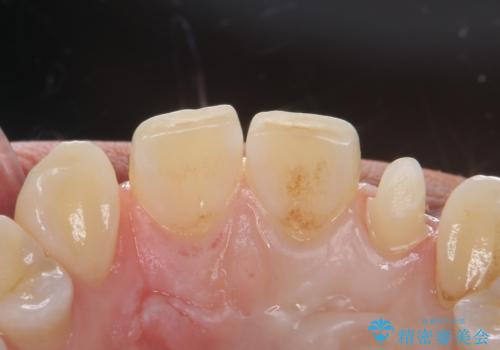

変色した前歯をキレイにしたい ジルコニアクラウンでの修復

- 左上の前歯の変色が気になるとのことで来院されました。

もともと小さい歯(矮小歯)に樹脂が盛り足されている状態でした。

今後の変色をなくすために樹脂ではなくセラミックでの治療を行います。